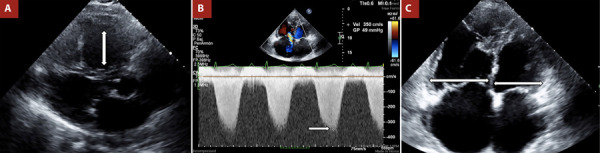

肺动脉高压的诊断方法采用心脏成像,特别是超声心动图,提供了一个实用的,容易获得的,高度有价值的工具。它有助于建立初步诊断的可能性,提供预后信息,并支持病原学评估。搅动生理盐水对比试验,也被称为气泡对比超声心动图,不仅可以帮助确诊,而且可以描述病情并确定肺动脉高压的各种潜在原因。

The diagnostic approach to pulmonary hypertension using cardiac imaging, particularly echocardiography, provides a practical, accessible, and highly valuable tool. It helps establish the initial diagnostic probability, offers prognostic information, and supports aetiological assessment. The agitated saline contrast test, also referred to as bubble contrast echocardiography, can aid not only in confirming the diagnosis but also in characterising the condition and identifying various underlying causes of pulmonary hypertension.